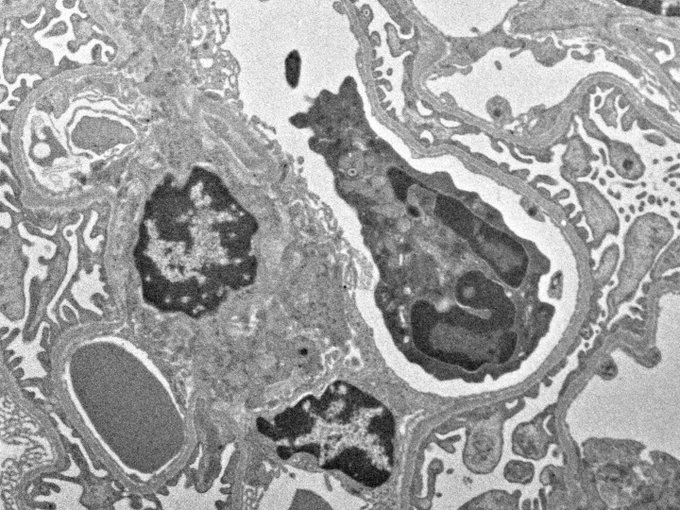

障害受けポドに健康ポドがトンネルナノチューブ(TNT)を介してミトコンドリアを受け渡す回復機構があるらしい

Mitochondria transfer system via tunneling nanotube rescues injured podocytes